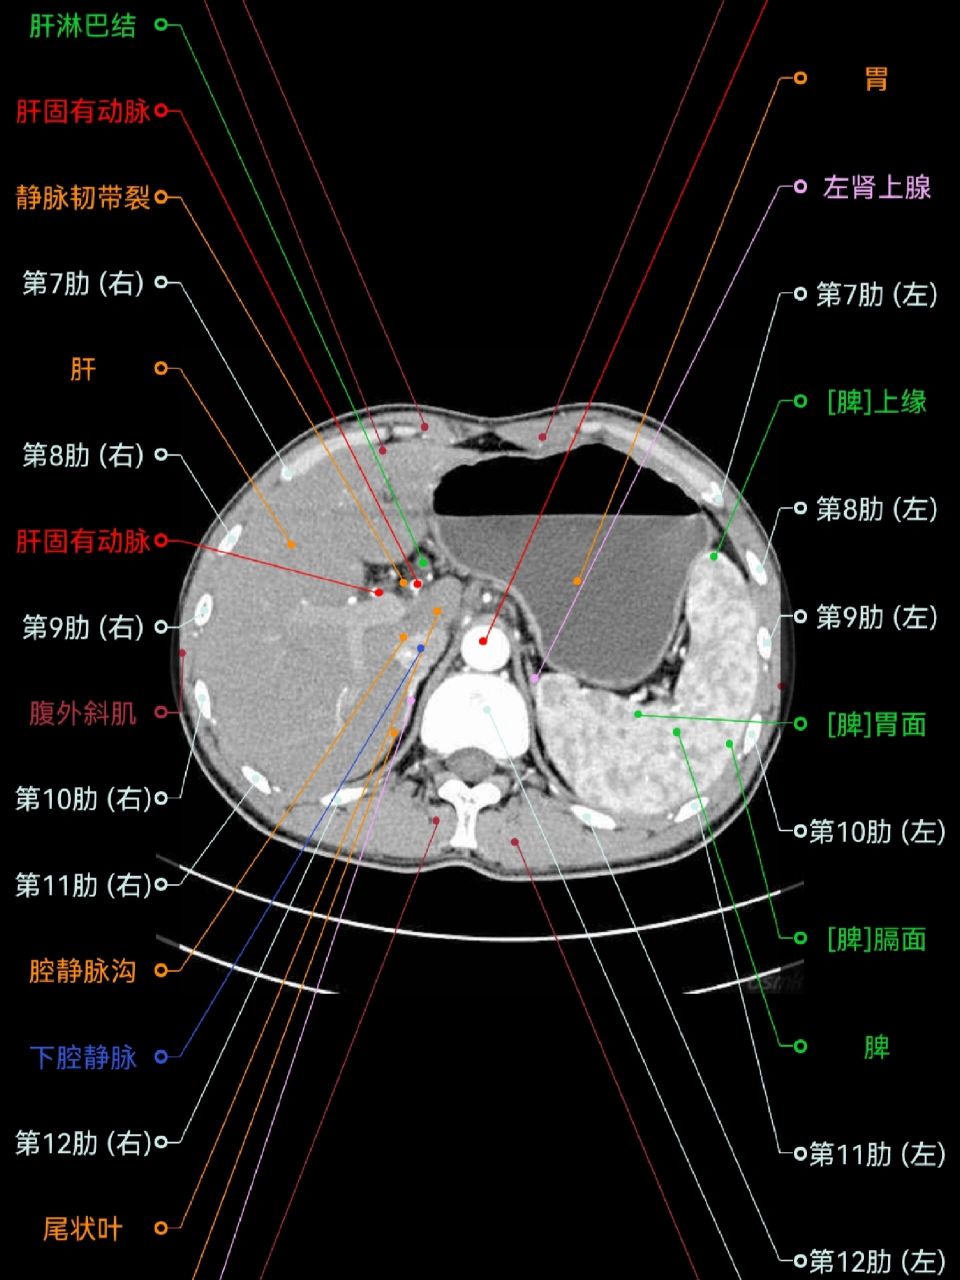

肝脏分段ct解剖 左肝:外侧段(s2/s3)与内侧段(s4a/s4b)沿镰状韧带

肝脏分段口诀与ct 追踪肝静脉,尾叶单独记 肝中静脉分左右 肝右静脉分

必须收藏!最详细的肝脏ct分段解剖逐帧播放!